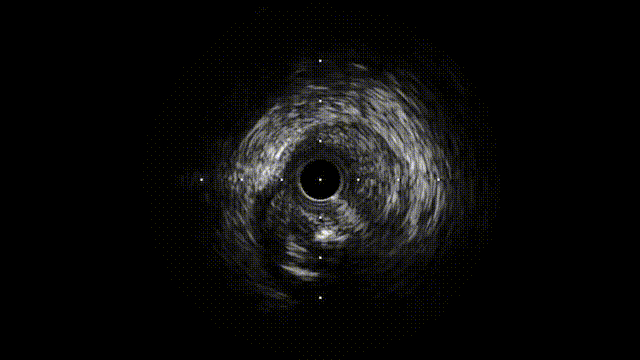

IVUS确诊夹层特征(图1F-G,视频3):

真腔受假腔压迫,假腔延伸至钙化斑块深部

LAD开口内膜撕裂,左主干未见明显夹层

图 1. 术中冠状动脉造影、IVUS及随访造影

F-G. IVUS:真腔受压,假腔延伸至钙化后方,内膜撕裂(黑色箭头)

J. IVUS:真腔扩大,多通道形成

在疑似夹层远端处,也以额定压力扩张灌注球囊以建立真-假腔交通,实现开窗(图 1I)。IVUS显示真腔扩大,真腔与假腔之间有多个连通,随后胸痛和 ST 段抬高缓解(图 1J、视频4)。冠状动脉造影显示LAD血管腔扩大,血流恢复至 TIMI 3 级。